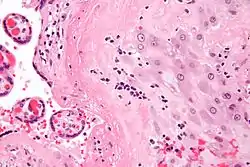

| Micrograph of a chronic deciduitis, showing the characteristic plasma cells. H&E stain. | |

Chronic deciduitis is a type of long-lasting inflammation that arises in pregnancy and affects the endometrial stromal tissue (decidua).

It is associated with preterm labour.[1] The diagnosis rests primarily on the presence of plasma cells.[2]